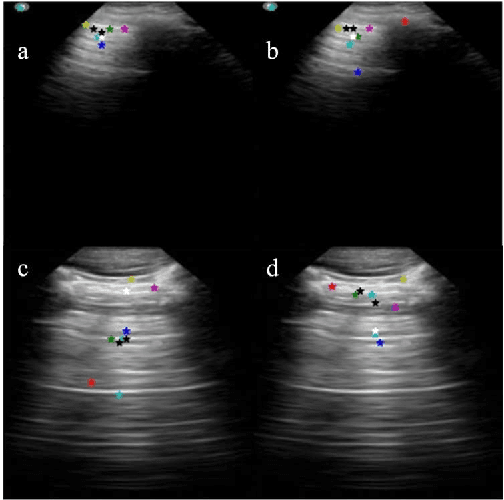

Abstract:Lung ultrasound (LUS) is an increasingly popular diagnostic imaging modality for continuous and periodic monitoring of lung infection, given its advantages of non-invasiveness, non-ionizing nature, portability and easy disinfection. The major landmarks assessed by clinicians for triaging using LUS are pleura, A and B lines. There have been many efforts for the automatic detection of these landmarks. However, restricting to a few pre-defined landmarks may not reveal the actual imaging biomarkers particularly in case of new pathologies like COVID-19. Rather, the identification of key landmarks should be driven by data given the availability of a plethora of neural network algorithms. This work is a first of its kind attempt towards unsupervised detection of the key LUS landmarks in LUS videos of COVID-19 subjects during various stages of infection. We adapted the relatively newer approach of transporter neural networks to automatically mark and track pleura, A and B lines based on their periodic motion and relatively stable appearance in the videos. Initial results on unsupervised pleura detection show an accuracy of 91.8% employing 1081 LUS video frames.